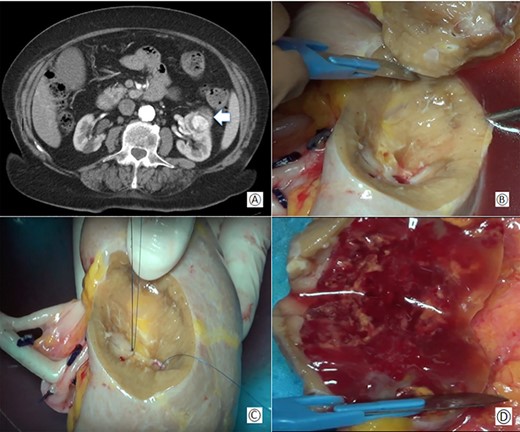

(A) Preoperative computed tomography: the white arrow shows the renal mass; (B) removal of the tumor during bench surgery; (C) suture of the renal calices during bench surgery; (D) macroscopic examination of the surgical piece.

The renal capsule was incised and the tumor was resected with at least 1 cm margin of healthy parenchyma, with microscopic frozen section examination negative for neoplastic residue (Fig 1B–D). The sectioned vessels were tied with polypropylene 6–0 (Ethicon®), while the renal calices and the pelvis were sutured with a polypropylene 7–0 running suture (Ethicon®) (Fig. 2A and B). The kidney was repositioned in its natural location (Fig. 2C). End-to-end artery anastomosis with polypropylene 7–0 separate stitches and end-to-end vein anastomosis with two running sutures in polypropylene 6–0 were performed. Double J silicone catheter (Coloplast, Bologna) was inserted and the ureteral stumps were anastomosed with PDS 6–0 (Ethicon®). The hemostasis on the residual renal parenchyma was completed with polypropylene 6–0 separate stitches and with a hemostatic sponge (TachoSil®- Nycomed, Konstanz, Germany). Two drains were placed anteriorly and posteriorly to the surgical site.